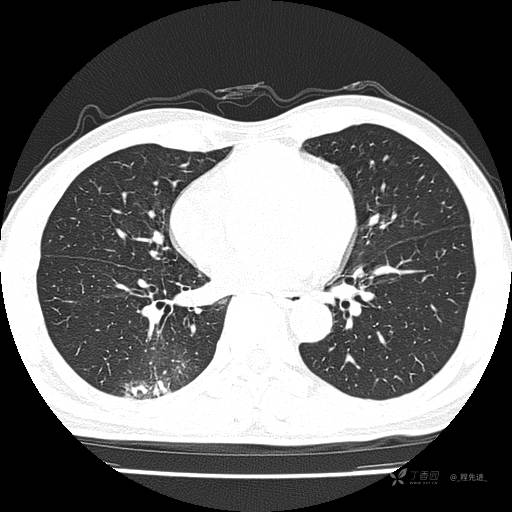

2月特别精彩病例|咳嗽、咳痰20余天,典型病例分享【结果已公布】

患者年龄:51岁

主诉:咳嗽、咳痰20余天

简要病史:20余天前开始出现咳嗽、咳痰症状,阵发性刺激性咳,白色粘痰,不易咳出,无发热,无咯血,无恶心、呕吐等不适,未诊治,咳嗽、咳痰症状持续存在。

体格检查:T:36.3 ℃ P:79 次/分 R:20 次/分 BP:128/64 mmHg,神志清楚,呼吸平稳,双肺呼吸音粗,右下肺闻及细湿性啰音。心率79次/分,节律整齐,各瓣膜听诊区未闻及病理性杂音。腹部未见异常,双下肢无水肿。

辅助检查:我院门诊胸部CT示:如下。心电图:窦性心律;正常心电图。